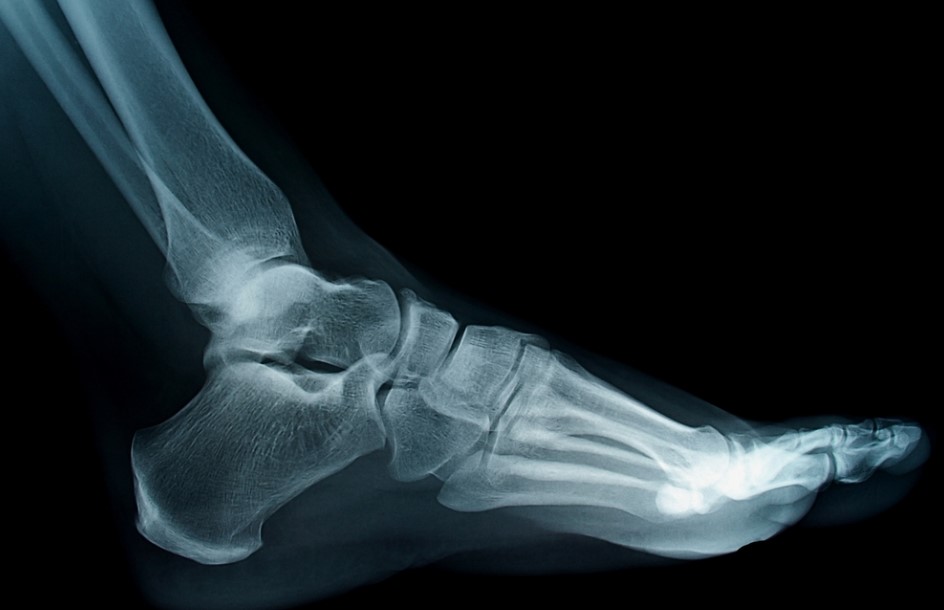

There are pre-surgery costs as well as post-surgery costs. The pre-surgery costs include appointments with specialists, diagnostic tests such as X-rays or CT scans, and prescription medication.